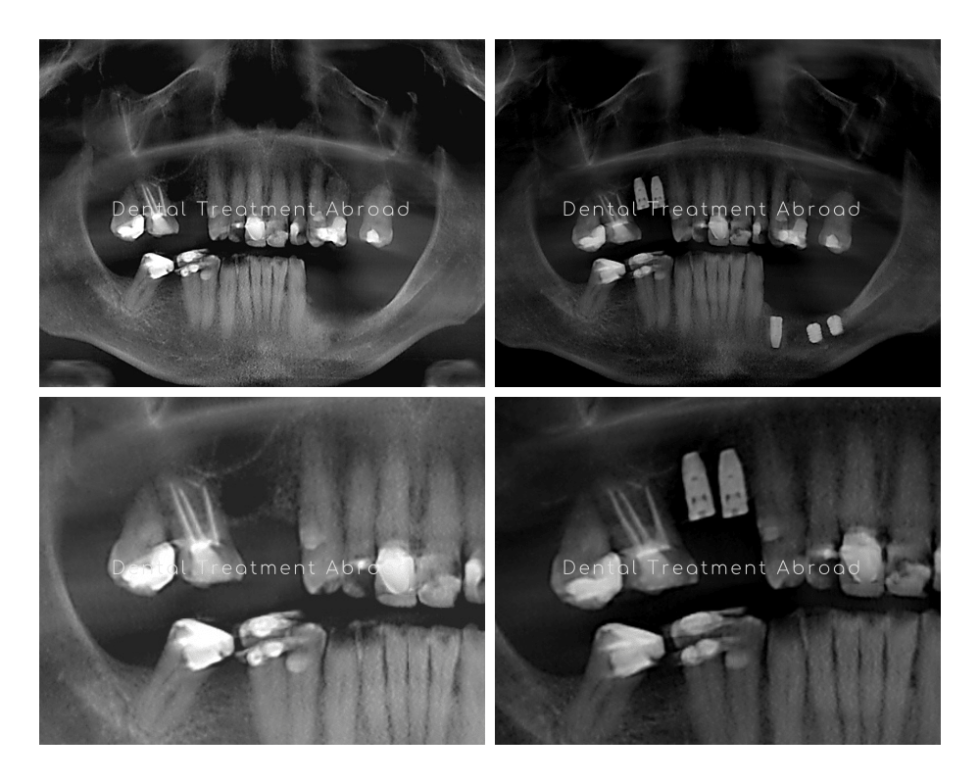

A, Horizontal bone loss around a dental implant. B, The of the Implant Bone Loss Treatment The level of bone loss that can be used to predict. Marginal bone loss is a key factor in the development of peri‐implantitis. Bone loss rate could be utilized as a reliable diagnostic tool for evaluating prognosis after surgical treatment, regardless of surgical method. As such, researchers and clinicians are in need of finding. The surgical treatment allowed complete access. Implant Bone Loss Treatment.